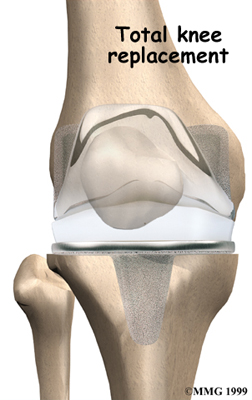

Artificial Knee Replacement

An artificial knee replacement is the ultimate solution for advanced knee OA.

Surgeons prefer not to put a new knee joint in patients younger than 60. This is because younger patients are generally more active and might put too much stress on the joint, causing it to loosen or even crack. A revision surgery to replace a damaged prosthesis is harder to do, has more possible complications, and is usually less successful than a first-time joint replacement surgery.

Related Document: FYZICAL Albuquerque's Guide to Artificial Joint Replacement of the Knee